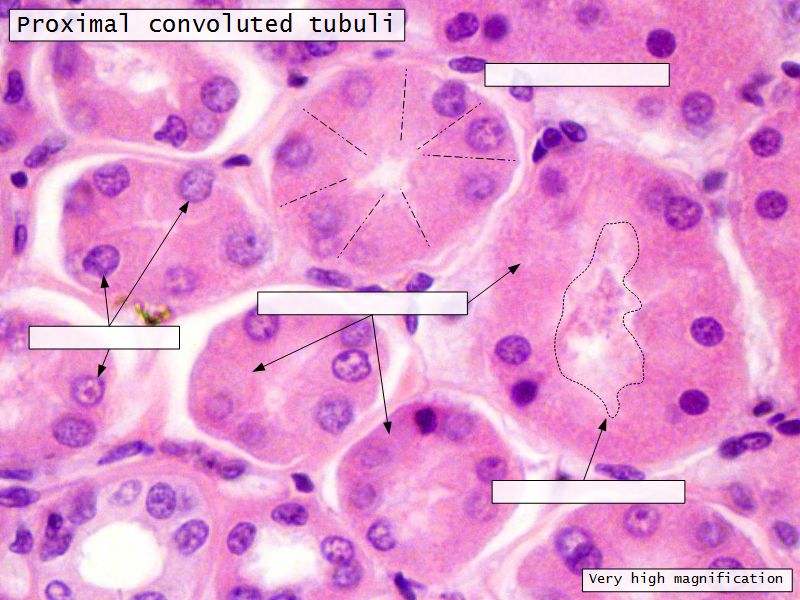

Proximal convoluted segment

- Longest part of nephron

- Wide triangular cell

- Spherical nucleus

- Indistinct cell borders

- Luminal surface

- Striated brush border